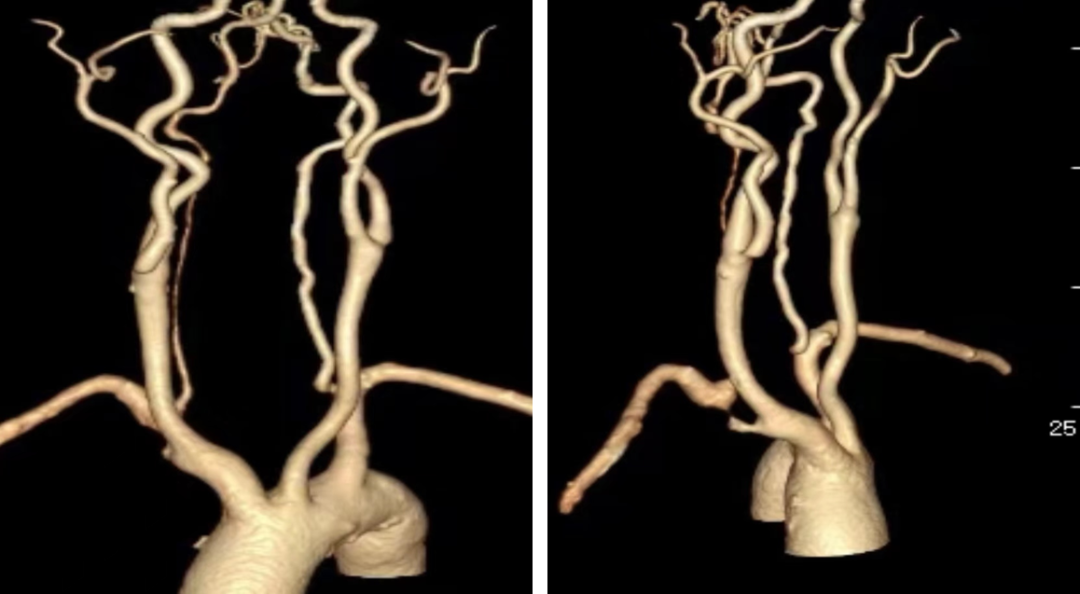

图:弓上病变

核心技术:CTA三维重建与投射角度模拟

本技术的核心在于利用CTA原始数据进行三维重建,在工作站上模拟术中造影机的各种投照角度(如左前斜LAO、右前斜RAO、加头位CRA、加足位CAU),从而在术前预先确定“最佳工作角度”。

回顾了2021年至2024年间,共39例应用CTA重建评估右锁骨下动脉病变的病例。

★ 投射角度分布

37例(94.9%)的最佳角度为右前斜位(RAO),但具体角度变化较大,需辅以不同的头位或足位。另外2例(5.1%)为左前斜位(LAO)。

图:右前斜位

★ 前瞻性验证

12例复杂病例在术前进行了针对性的CTA角度模拟,术中造影证实模拟角度与最佳工作角度完全一致。该技术显著帮助了导丝导管通过和支架的准确释放。

图:复杂病例